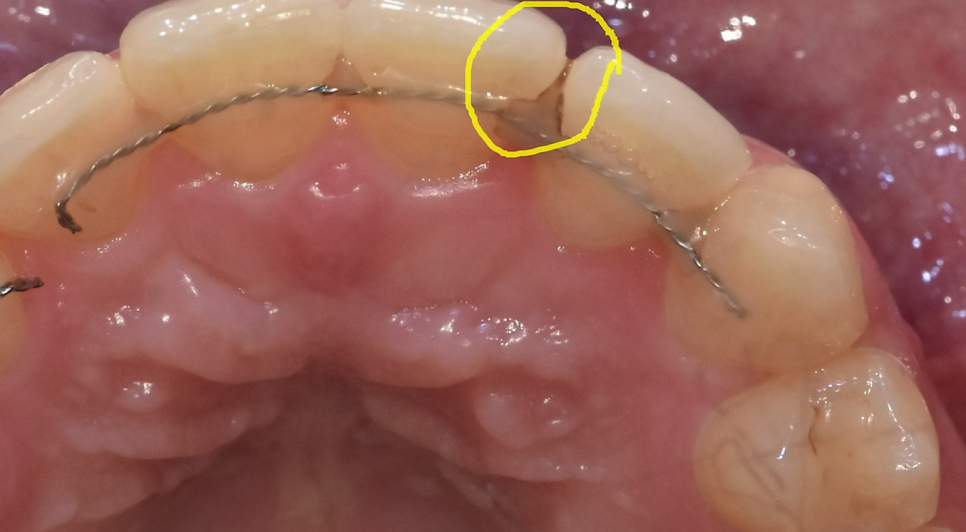

- 충치 및 잇몸 질환 위험 증가

교정 장치를 착용하면

치아 사이에 음식물과 플라그가 쉽게 끼면서

충치와 잇몸 염증이 발생할 가능성이 높아집니다.

250208 유지장치 사이에 생긴 충치ㅠㅠ

양치를 꼼꼼히 하셔야겠죠~??

투명교정장치는 그나마 괜찮은데...

고정식 장치를 사용하는 경우 칫솔질이 어려워

치아 교정이 끝나면 대량의 충치가 발생하는 경우가 많답니다.

때문에 치간칫솔, 치실을 교정 중에 필수로 사용하셔야하납니다!!